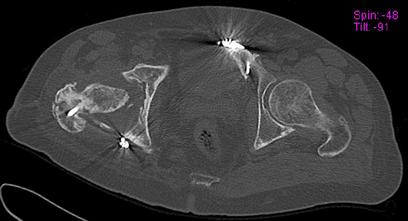

Пациент 49 лет, паровозная травма 23.2.2006, получил вертикальная нестабильное повреждение таза, разрыв левого крестцово-подвздошного сочленения, перелом лонной, седалищной костей слева, T-образный оскольчатый перелом правой вертлужной впадины с переломом заднего края, вывих правого бедра, посттравматическая пояснично-крестцовая плексопатия с обеих сторон, паралич мышц правой голени.

В день травмы - вправление вывиха, скелетное вытяжение, 14.3.2006 чрескостный остеосинтез таза. 20.4.2006 остеосинтез правой вертлужной впадины пластинами, осложнившийся нагноением межмышечной гематомы правой ягодичной области. Получал консервативное лечение, было достигнуто полное заживление раны. 24.7.2006 введены илиосакральные винты слева. С декабря 2006 года и по настоящее время ходит на костылях без опоры на правую ногу. Планируется THA. Помогите определиться с вариантом костной пластики? И какую укрепляющую конструкцию использовать?